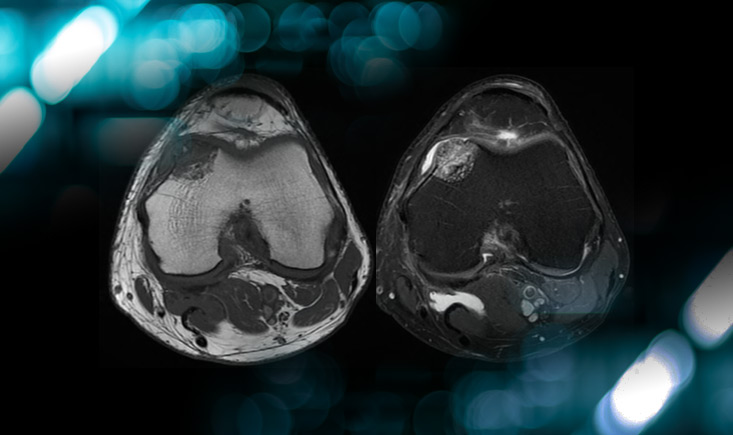

• CT-scan: Subchondral osteolytic lesion of the medial femoral condyle, with cortical breach.

• MRI: HypoT1, hyper T2, gado +

CT-scan: Subchondral osteolytic lesion of the medial femoral condyle, with cortical breach.